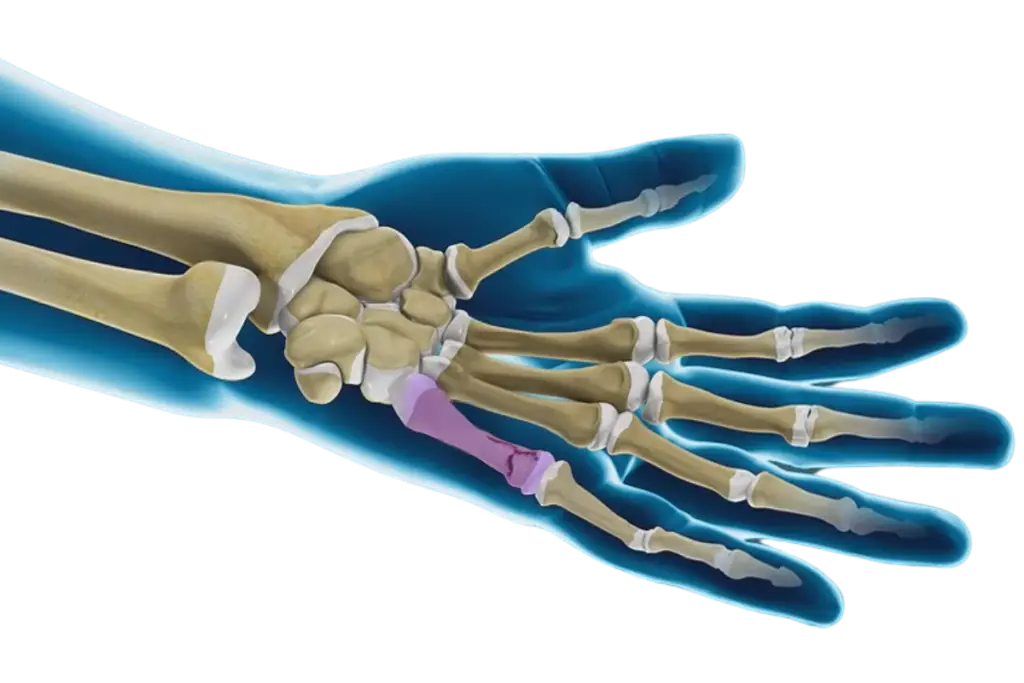

A hand fracture is a break or crack in one or more of the bones in your hand. The human hand contains 27 bones, including:

14 phalanges (finger bones).

5 metacarpals (middle bones of the hand).

8 carpal bones (bones in the wrist).